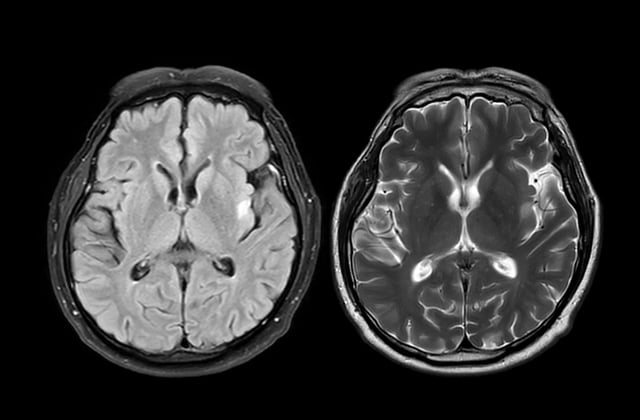

• ASA-PD uses ultra-sensitive fluorescence microscopy that maximizes signal and reduces background, enabling analysis of millions of individual aggregates across brain regions.